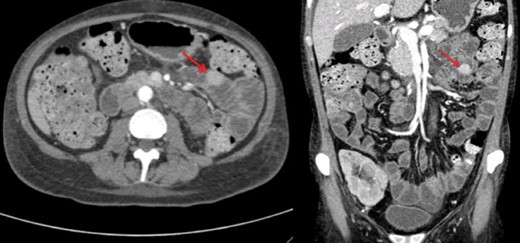

A renal biopsy was performed and showed atypical glomerulopathy with immune complexes. An autoimmune panel was negative. Investigations were performed to assess the presence of an inflammatory or infectious process. An abdominopelvic computed tomography (CT) scan revealed a hyperdense mass in the small bowel (Fig. 1). CT enterography further showed a 2 cm homogeneous jejunal lesion with no extraluminal extension (Fig. 2). Positron emission tomography scan displayed no hypermetabolism in the small bowel or in the renal allograft. Differential diagnosis included gastrointestinal stromal tumor and leiomyoma, but due to the transplant immunosuppression and the Epstein-Barr viral load of 16 596 copy/mL, a post-transplant lymphoproliferative disease (PTLD) was highly suspected.